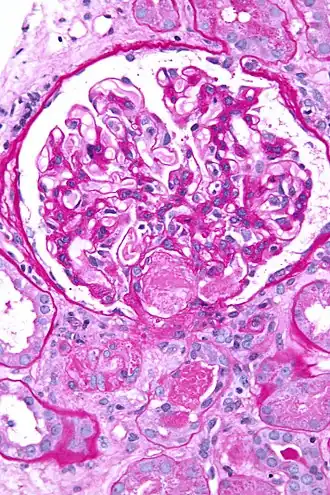

![]() Микрофотография биоптата почки при острой тромботической микроангиопатии, вызванной ДВС-синдромом. Тромб находится в воротах клубочков (центр изображения). | |